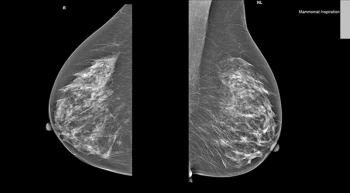

The National Comprehensive Cancer Network (NCCN) guidelines on breast cancer now allow physicians to pinpoint the women who are most likely to benefit from post-mastectomy radiation using the latest targeted testing techniques.